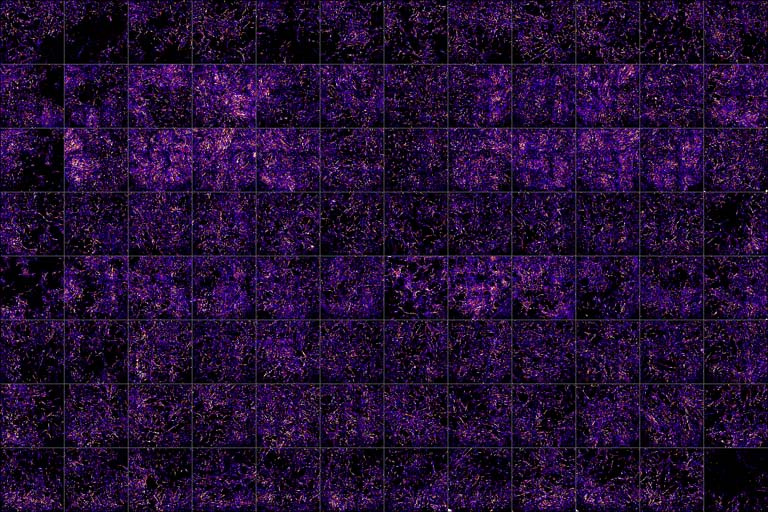

This is a large scale experiment to find molecules that increase or decrease cancer growth. We measure each molecule’s activity by taking an image of cells grown in culture (here, cells taken from a desmoid tumor, a rare type of cancer). Based on how densely the cells are growing (here, visualized as a gradient from purple to yellow), we can assess the activity of each molecule. Such microscopy-based workflows enable these large scale screening experiments in many more cancers than other traditional methods.